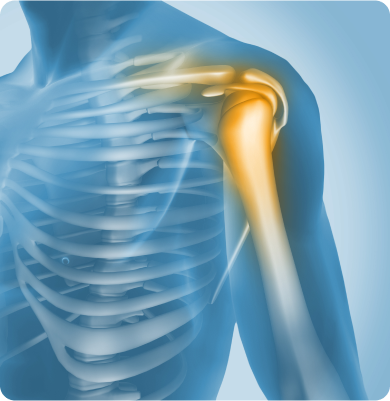

어깨 관절염

어깨 관절 내 연골이 점진적으로 닳아 없어지는 퇴행성 질환

주요원인

노화에 따른 관절 연골의 퇴행, 외상, 반복적인 어깨 사용, 과거 탈구나 회전근개 파열 등이 원인이 될 수 있습니다.

주요증상

• 어깨를 움직일 때 통증이 발생하고 점차 일상생활에서도 통증이 나타납니다.

• 팔을 위로 올리거나 뒤로 젖힐 때 움직임이 제한됩니다.

• 어깨에서 ‘딱딱’ 소리가 나거나 마찰음이 느껴지기도 합니다.